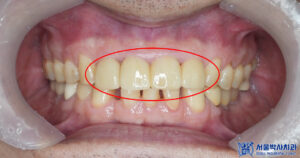

앞니는 심미적인 부위이기 때문에,

브릿지의 모양, 색상, 형태를

정밀하게 확인한 후에

영구접착을 진행했습니다.

환자분의 자연스러운 미소를 위해

세심한 조정을 거쳐

최적의 결과를 도출할 수 있도록

신경을 썼습니다.

마무리 후 사진입니다.

환자분께서는 시간이 많이 없으신

직장인으로 치과치료에 대한

부담이 많으셨으나,

최소내원 신경치료와 당일 신경치료로

세심하지만 속도감 있게

신경치료를 마무리해 드렸습니다.

자체 원내기공소에서

앞니 브릿지를 제작하였기에

시간을 단축시켜서 빠르게

치료를 마무리 하였습니다.

환자분께서 치료받고 나셔서

앞니 쪽 불편했던 부분이

많이 편안해지셨고,

브릿지도 마음에 든다고 하셨습니다.